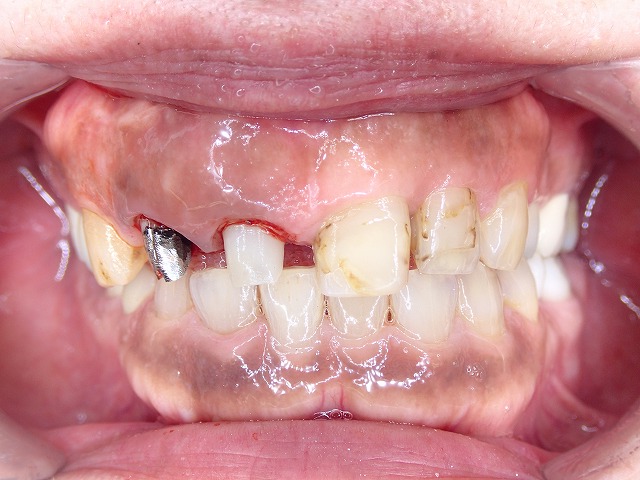

来院時の状態

問題の歯は、過去に根尖切除が行われており、被せ物がしばしば外れていました。

さらに、歯ぎしりの影響も強く、被せ物自体に大きな負担がかかっていました。

詳しく確認すると、根の先に近い部分は非常に厳しい状態で、

歯の保存が簡単ではないことが分かりました。

根尖切除の履歴のある歯が脱離して来院

歯ぎしりもひどく何度も脱離しています。

歯ぎしりでメタルボンドクラウンに

穴が空いています。